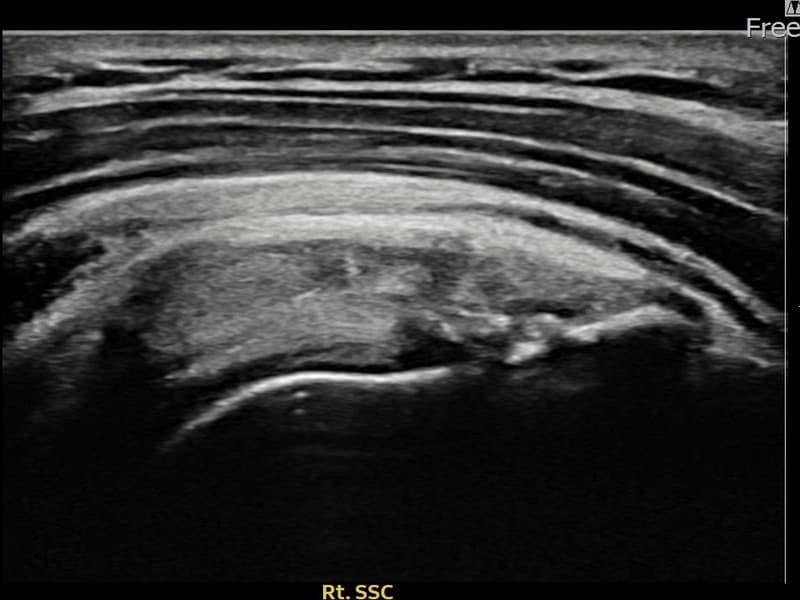

超声确认右侧 冈下肌腱 附着部部分撕裂(8.6mm × 4mm (肌腱厚度约45%缺损))。缩小缝合术后肌腱连续性恢复,患者回归正常生活。

术前超声确认右侧 冈下肌腱 附着部部分撕裂,右侧冈下肌腱回声不连续伴肌腱缺损(8.6mm × 4mm (肌腱厚度约45%缺损))。术后超声显示撕裂部位充满再生组织,肌腱连续性恢复,回声模式正常化。

该患者持续肩痛。详细超声检查确认右侧 冈下肌腱 附着部部分撕裂(缺损:8.6mm × 4mm (肌腱厚度约45%缺损))。在超声引导下实施非手术缩小缝合术。术后佩戴支具约4-6周,随后进行分阶段康复锻炼。随访超声确认肌腱连续性恢复、结构稳定,患者顺利回归日常生活。